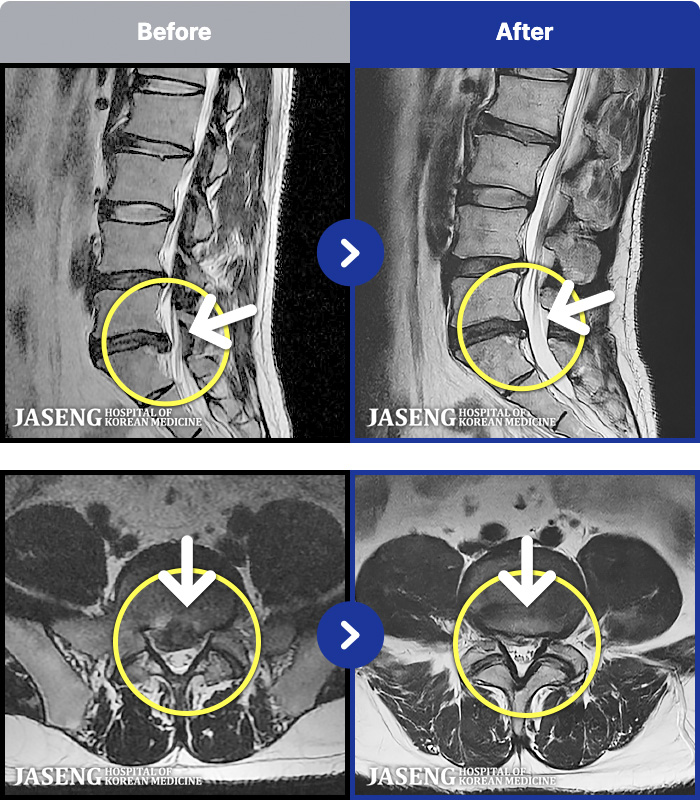

54 MRI ũ ʸ Ȯϼ.

ȯںп Ǹ ǿ ԿǾ, ο ġ ۿ Ƿ ġḦ Ͻñ ٶϴ.